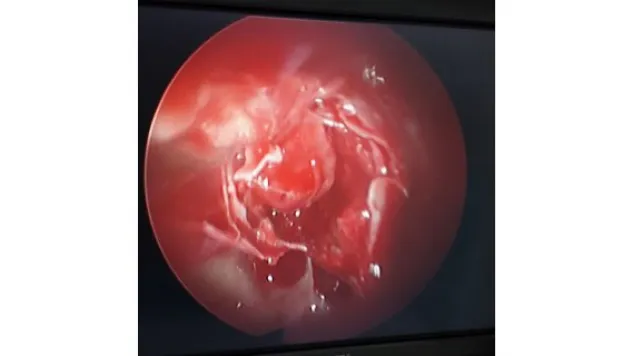

Beyin tümörü burundan girilerek alınıyor